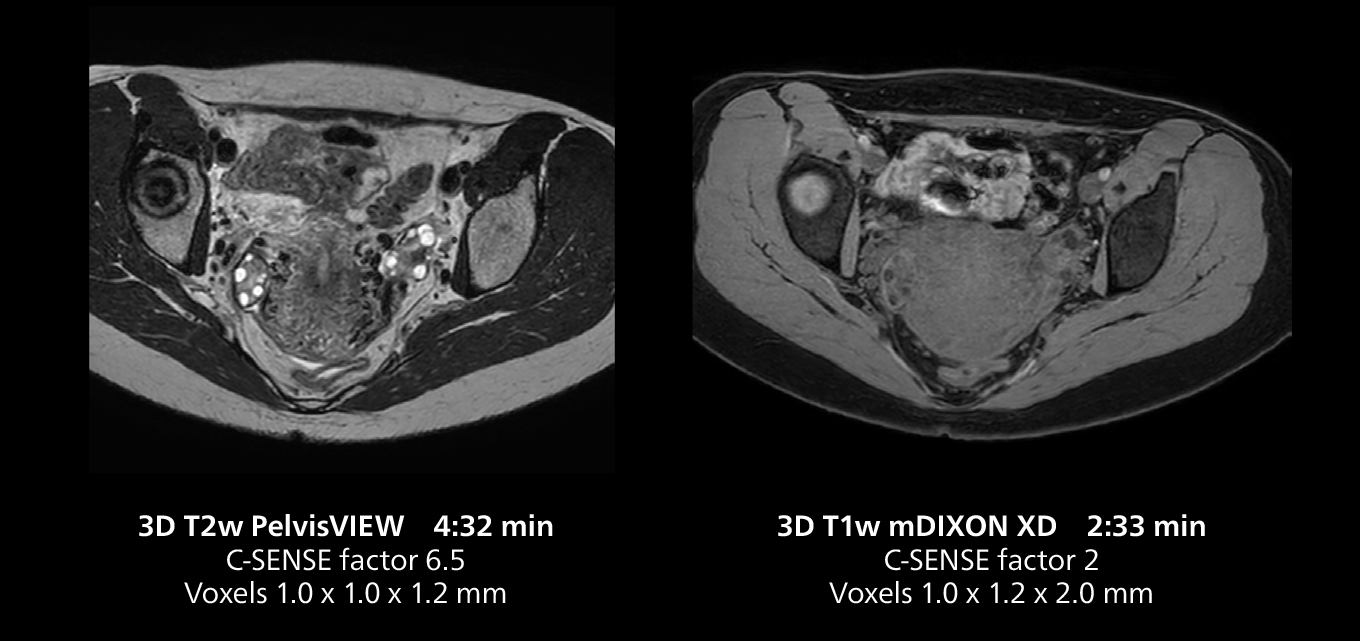

Le Dr Gellée estime que la fiabilité des acquisitions en respiration libre est “la caractéristique qui fait la plus grande différence au quotidien. Les séquences 3D en respiration libre sont très reproductibles et l’acquisition axiale est très bonne. Par exemple, pour l’endométriose, qui est l’un de mes domaines de prédilection, elles offrent un contraste élevé et une bonne résolution, ce qui me permet de voir les moindres détails. Nous utilisons également la respiration libre pour l’imagerie du foie et du pancréas. Dans les examens du foie multiphases, la respiration libre 4D offre une résolution temporelle de 3 secondes, permettant une acquisition dynamique avec plusieurs phases artérielles.”

Le système MR 5300 doté de Compressed SENSE est jusqu’à 50 %** plus rapide pour de nombreux examens. Il permet de réaliser des examens de routine en moins de 5 minutes et des examens du corps entier en moins de 20 minutes. Saint-Augustin a su profiter de cette rapidité pour créer des protocoles très efficaces. La procédure d’AVC standard de l’hôpital ne dure qu’environ 8 minutes, et les examens ORL standard, la classification PIRADS de la prostate et les examens de l’endométriose ne durent tous qu’environ 10 minutes***.

“Les séquences 3D sont plus rapides”, affirme le Dr Gellée. “Avec Compressed SENSE, nous pouvons remplacer deux ou trois acquisitions 2D par une acquisition 3D de haute qualité. Des orientations supplémentaires de haute qualité peuvent être obtenues par post-traitement de l’ensemble des données 3D, ce qui permet d’économiser du temps d’acquisition.”

“La rapidité est également bénéfique pour les patients. Par exemple, si une patiente présente un fibrome, j’aime inclure une acquisition post-gadolinium, car connaître la cinétique de prise de contraste facilite le diagnostic. Sans cette séquence, nous avons parfois besoin d’un autre rendez-vous pour effectuer une acquisition supplémentaire, mais je préfère vraiment tout faire en une seule fois. L’ajout de cette séquence post-gadolinium est donc plus utile pour moi que la réduction de la durée de l’examen.”